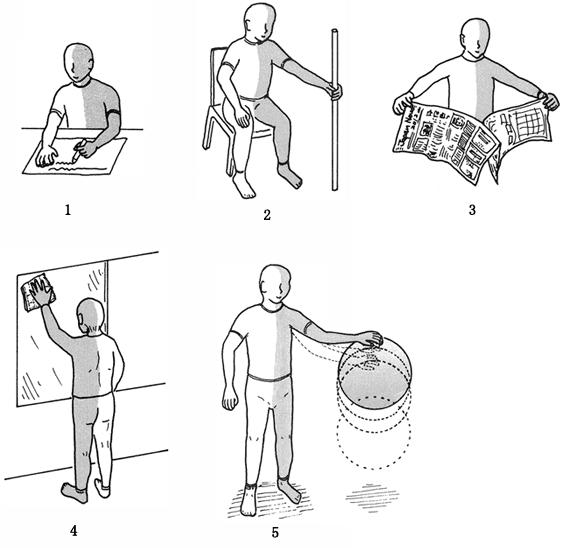

60歳の男性。左片麻痺。脳梗塞発症後1か月経過。認知機能や感覚機能に問題はない。ブルンストローム法ステージは上肢II、下肢V。上肢運動機能の回復促進で適切でないのはどれか。

1

2

3

4

5